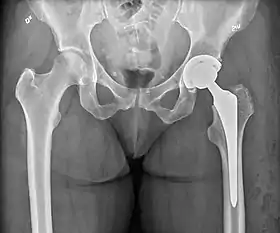

An X-ray showing a left hip (right of image) that has been replaced, with the ball of this ball-and-socket joint replaced by a metal head that is set in the femur and the socket replaced by a cup

Hip replacement is a surgical procedure in which the hip joint is replaced by a prosthetic implant, that is, a hip prosthesis. Hip replacement surgery can be performed as a total replacement or a hemi/semi(half) replacement. Such joint replacement orthopaedic surgery is generally conducted to relieve arthritis pain or in some hip fractures. A total hip replacement (total hip arthroplasty or THA) consists of replacing both the acetabulum and the femoral head while hemiarthroplasty generally only replaces the femoral head. Hip replacement is one of the most common orthopaedic operations, though patient satisfaction varies widely. Approximately 58% of total hip replacements are estimated to last 25 years.[1] The average cost of a total hip replacement in 2012 was $40,364 in the United States, and about $7,700 to $12,000 in most European countries.[2]